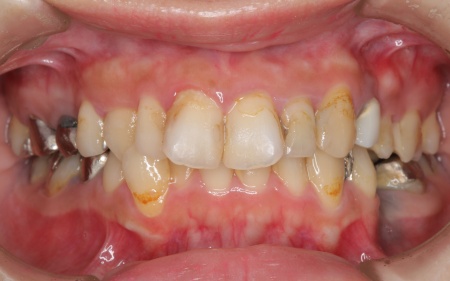

20代女性 ワイヤー矯正で歯並びを整えて虫歯治療やインプラント治療で口腔内全体を改善した症例

詳しく拝見したところ、下の前歯4本を除くほぼすべての歯に虫歯が認められました。 また、左上奥歯1本と左下奥歯1本が欠損しており、その影響で噛み合わせのバランスが崩れているため、噛んだときの痛みにつながっていると考えられます。 このまま放置すると、虫歯が進行したり、欠損部周囲の歯が動いて噛み合わせがさらに不安定になったりするリスクがあるため、虫歯を含めた口腔内全体の治療が必要だと診断しました。 |

診断結果をお伝えしたうえで、以下2つの治療方法を提案しました。 ①歯並びを整えず、必要な部分のみを治療する方法 ②矯正治療で歯並びと噛み合わせの土台を整えたうえで、口腔内全体の治療を行う方法 それぞれのメリット・デメリットをお伝えしたところ、患者様は②の矯正治療を含めた総合的な治療を行う方法を選択されました。 はじめに、歯の表面にブラケットと呼ばれるボタン状の装置を接着し、そこにワイヤーを通して歯を動かすワイヤー矯正を開始しました。治療期間中は定期的に状態を確認し、計画通りに歯が動くよう調整を重ねています。 虫歯が生じている歯に対しては、虫歯部分を丁寧に除去し、歯の形を整えました。その後、被せ物を作製するために型取りを行い、後日完成した被せ物を装着しました。 また、欠損していた左上奥歯1本と左下奥歯1本に対しては、インプラント治療を行います。 すべての治療工程を終えたあと、噛み合わせや見た目、被せ物の使用感に問題がないかなどを確認して、治療を終了しています。 |

治療前